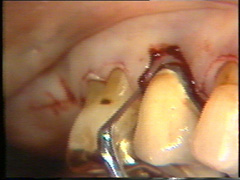

El  colgajo se levanta teniendo cuidado de no desgarrarlo.

En la superficie palatina del central, hay un defecto grande en la superficie de la raíz. Probablemente sea una fractura que ocurrió en relación con el accidente. El tejido de  granulación se  ha formado en el defecto que se limpia completamente. Postoperatoriamente es necesario poner apicalmente el colgajo en relación con el defecto de la raíz  para crear una condición higiénica manejable